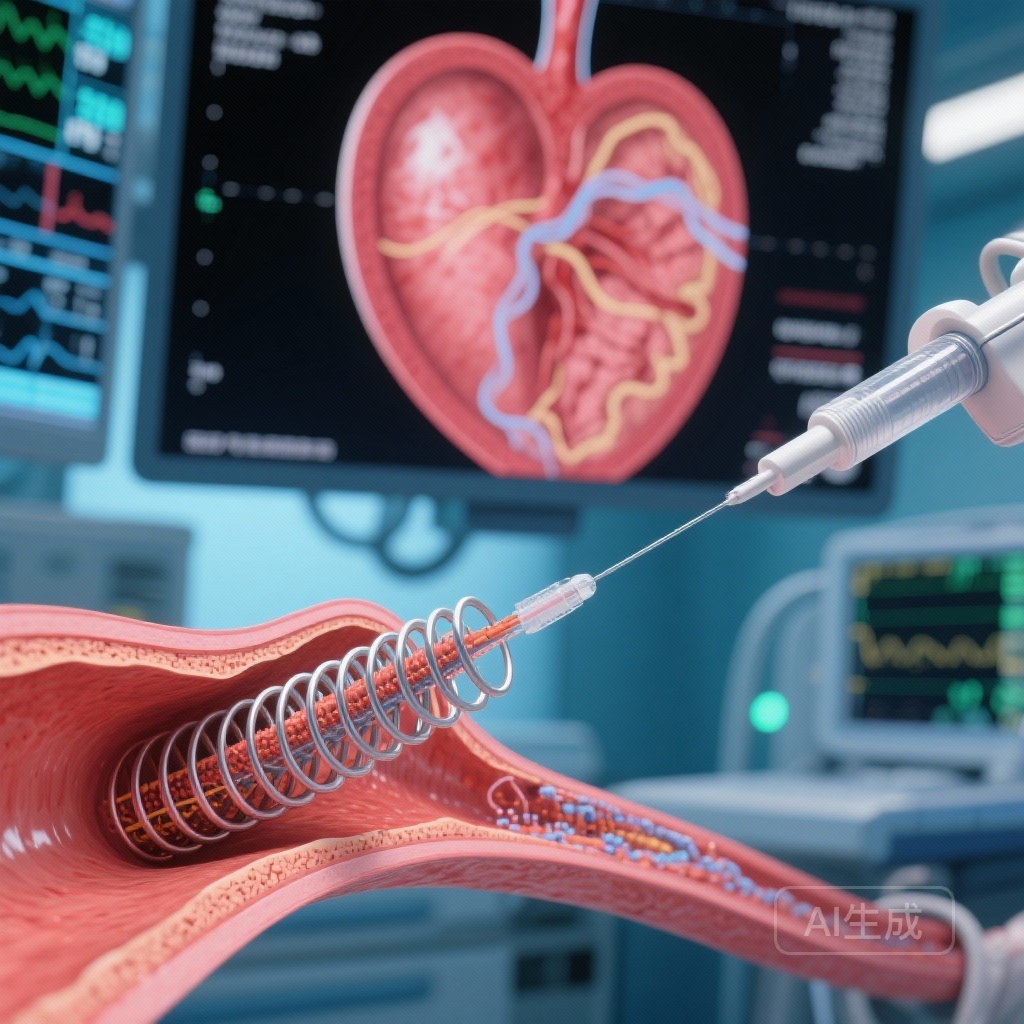

OCT-Guided PCI Achieves Greater Stent Expansion Than Angiography in Calcified Lesions: Findings from the CALIPSO Randomized Trial

In CALIPSO, OCT-guided PCI using predefined algorithms produced larger minimal stent area than angiography-guided PCI for moderate-to-severe calcified coronary lesions, with more targeted use of intravascular lithotripsy and no excess periprocedural safety signals.